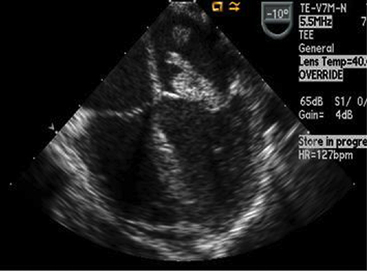

Although the ECG may not be helpful in the diagnosis of endocarditis (other than possible onset of new conduction disturbances), the echocardiogram often enables visualization of vegetations and is considered an essential tool in diagnosis. A negative echocardiogram, however, will not rule out the presence of endocarditis. The chest radiograph may show evidence of congestive heart failure and/or changes indicative of pulmonary embolic lesions or abscess.

The echocardiogram is required to rule out the presence of structural heart disease, and it will enable evaluation of heart size, ventricular contractility, and atrioventricular (AV) valve function. The echocardiogram also will confirm the presence of any significant pericardial effusion.